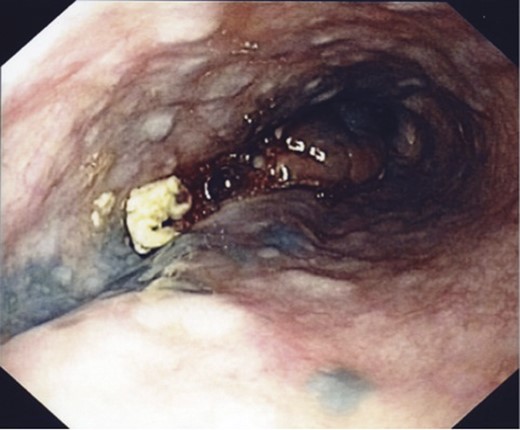

A 75-year-old male presented with a 2-month history of dysphagia, odynophagia and retrosternal post-prandial pain. He had no relevant medical history, and physical, dermatological and ophthalmological examinations proved unremarkable. Barium swallow showed filling defects in the distal oesophagus and subsequent endoscopy found an 8-cm bluish exophytic oesophageal lesion with numerous adjacent satellite lesions and moderate luminal stricturing (Fig. 3). A biopsy result indicated a poorly differentiated malignant melanoma. CT and PET showed an enlarged mediastinal node (not FDG avid) with no evidence of metastases.

An endoscopic view of the oesophageal melanoma with numerous adjacent satellite lesions.